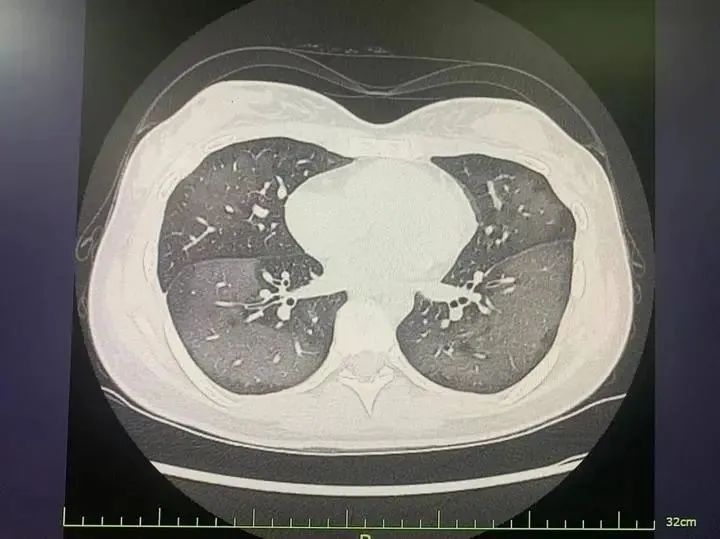

患者肺部CT

經CT檢查發現,麗麗的雙肺呈現大范圍白色樣病變,報告提示“白肺”,麗麗被診斷為“急性過敏性肺炎”。

急診科主任陸遠強主任醫師解釋,此類“白肺”與使用防曬噴霧時吸入的有害物質有關,噴霧中的某些化學成分會刺激誘發一系列過敏反應,從而導致廣泛的氣管、支氣管乃至肺水腫,讓肺部無法正常工作。

陸遠強主任介紹,“白肺”是指在胸部X片或肺部CT等影像學檢查中,看到患者肺部呈現大范圍的白色陰影。急診科接診的“白肺”患者,多見于年齡較大、免疫力低下、有慢性病史或多種疾病共存的人群,年輕人因吸入防曬噴霧變“白肺”的病例并不多見。